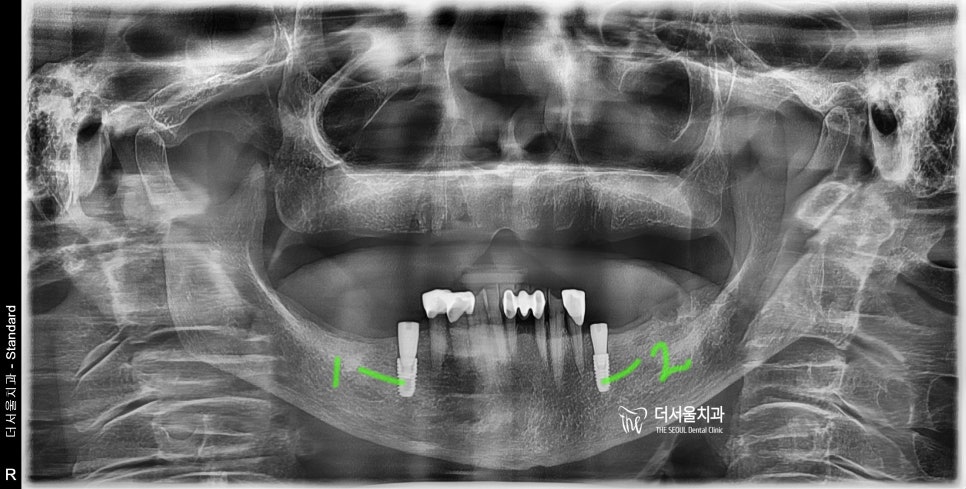

『임플란트 시술 결과』

남아있는 자연치아의 양 옆으로

나란히 1개씩 총 2개를 심어드렸습니다.

이후, CT를 찍어서 예상 된 위치에

임플란트가 잘 심겨졌는지 재 확인을 하죠.

사전 디지털 임플라늩 진단

뼈가 많이 위축이 되셔서,

여간 쉬운 일은 아니였었습니다.